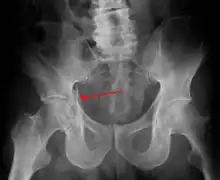

![]() | |

| Acetabular fracture as seen on plain X-ray |